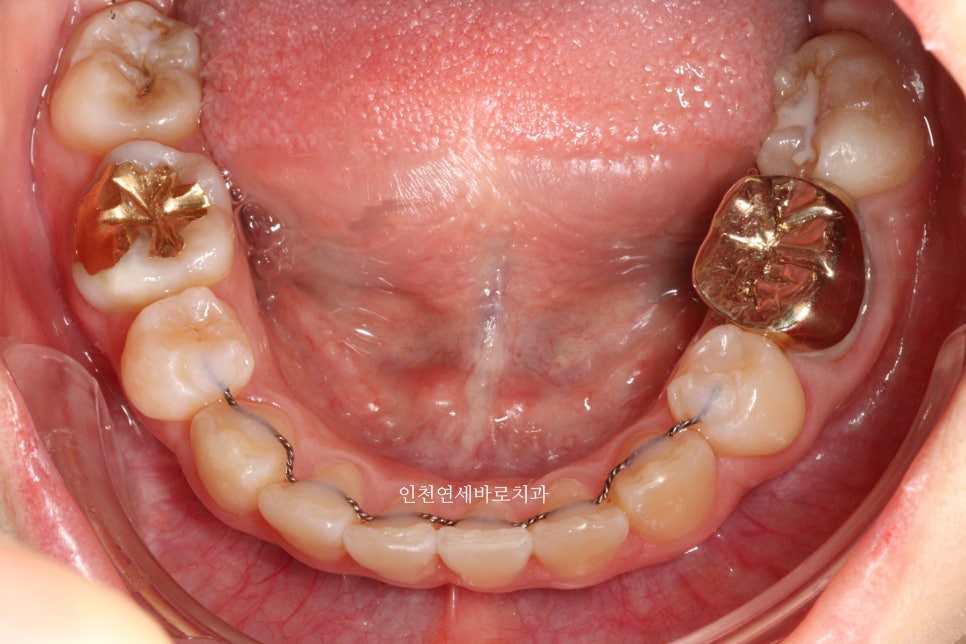

오늘은 교정이 끝난지 오래되어 재교정을 하고 싶어 내원했던 환자분 이야기 입니다.

예전에 중학생때 발치교정치료를 받았다고 합니다.

환자분의 나이는 이제 30대

약 15년만에 다시 교정치료를 결심하셨다고 합니다.

결혼을 앞둔 분이었고

앞니하나가 많이 틀어졌는데 점점 틀어진다고 하셨습니다.

철사 유지장치를 붙여놨었는데 오래전에 탈락 하고 다시 붙이지 않으셨다고 합니다.

변화모습입니다.

장치의 제작이 한달이나 걸리기 때문에 3/30이 처음 교정치료를 시작했던 날입니다.

약 3개월의 변화모습입니다.